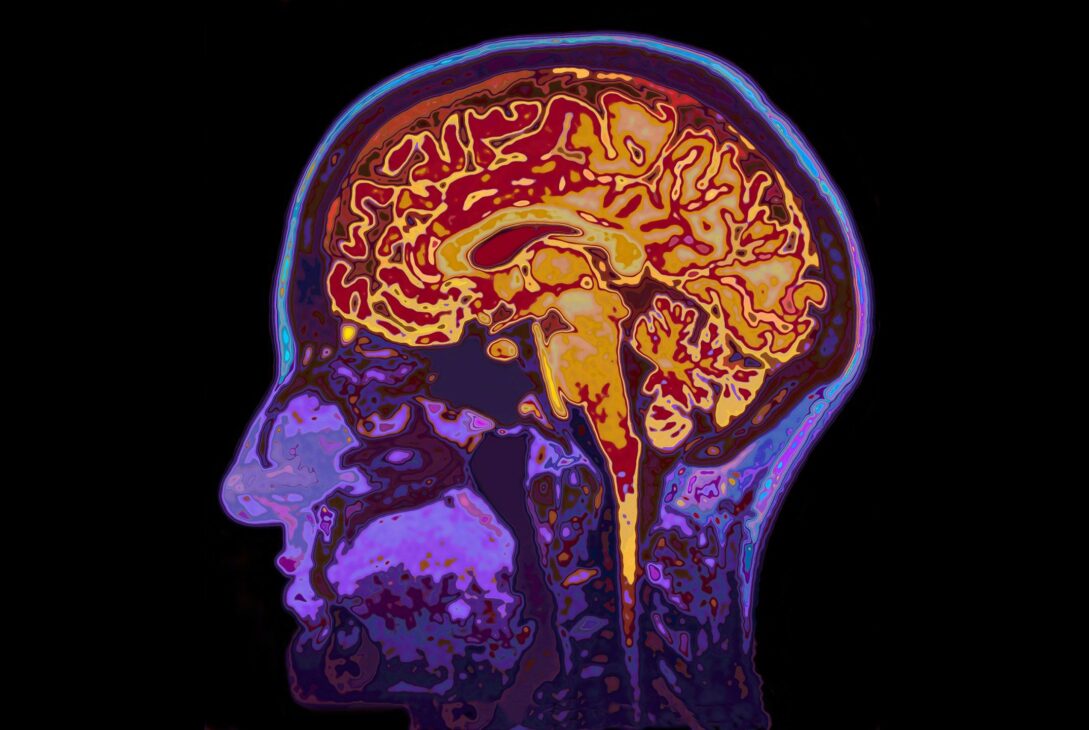

Emoțiile noastre, dincolo de transpirația palmelor sau bătăile inimii, au o hartă exactă pe care oamenii de știință au început să o descifreze. Un studiu recent al Universității din Hong Kong arată că intensitatea cu care trăiești o emoție este reflectată de o „semnătură” distinctă în creier, chiar și atunci când organismul nu răspunde vizibil.

- O echipă de la Universitatea din Hong Kong a identificat pentru prima dată o „semnătură cerebrală” clară a intensității emoționale conștiente, separată de reacțiile corpului.